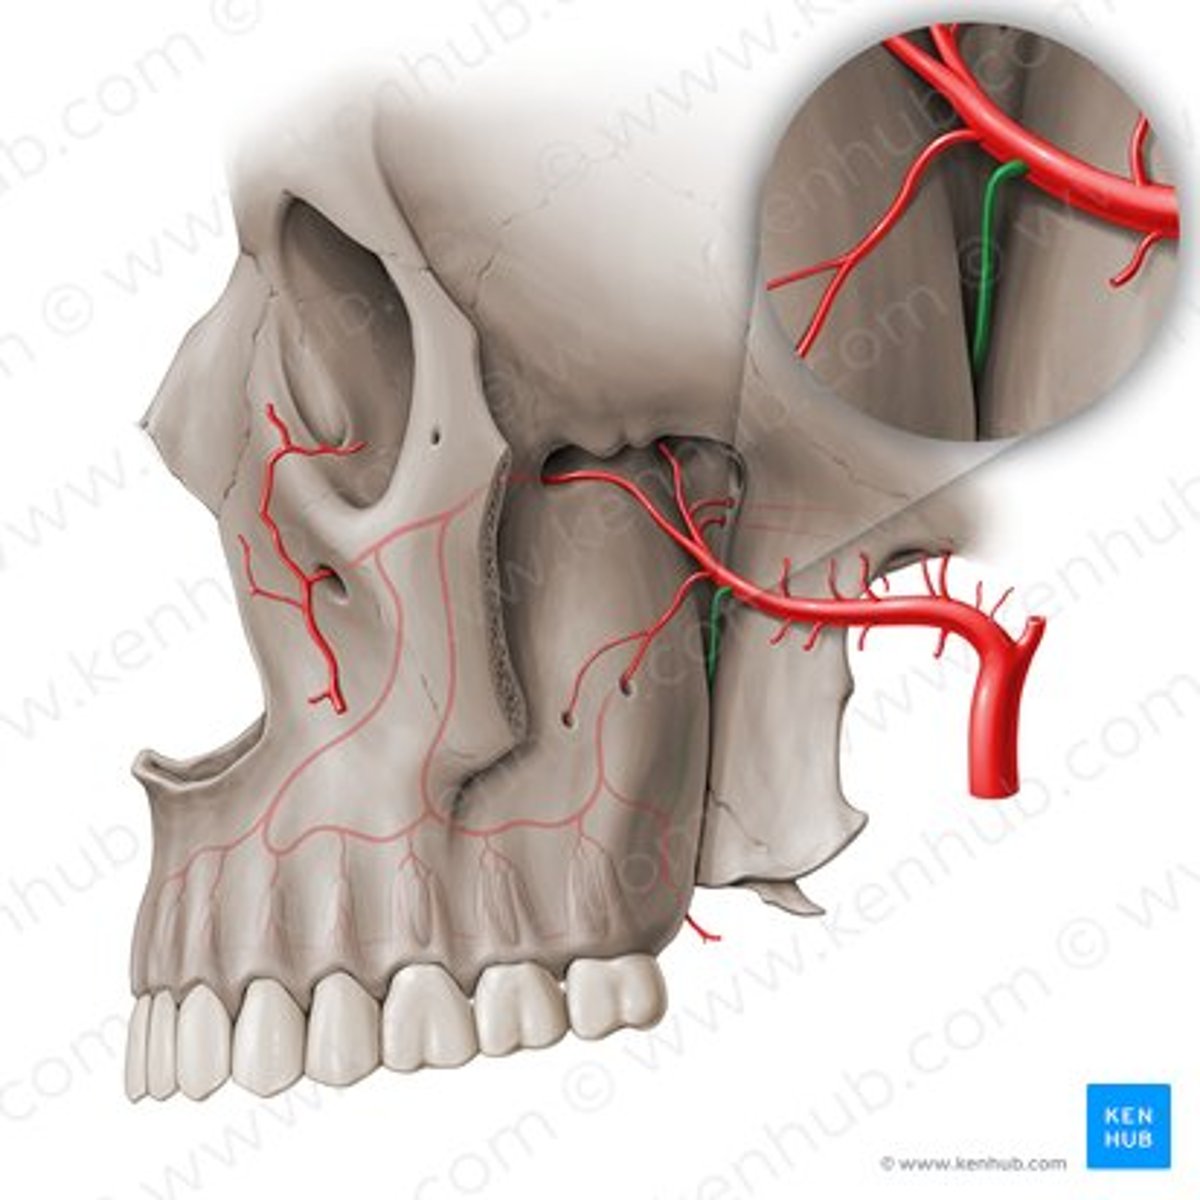

descending palatine artery

greater palatine artery

lesser palatine artery

lingual artery

lingual artery

inferior alveolar artery

buccal artery